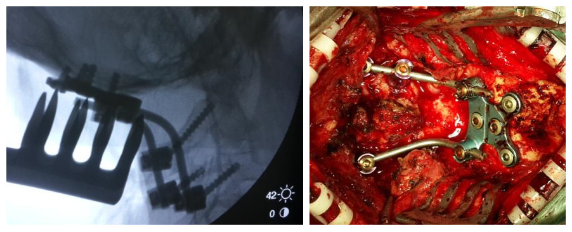

全麻后,显微镜下行颈后路减压+寰枢椎(C1~2)复位椎弓根螺钉钛棒内固定+植骨融合术。术中C臂下行C1~2复位椎弓根置钉。术后三个月复查见椎管减压后脊髓位置良好,寰枢椎脱位复位,局部可见骨融合。患者自述四肢麻木无力感明显好转。

7术中片子

全麻后,显微镜下行颈后路减压+枕颈撑开复位椎弓根侧块(左侧枕骨-C2~3,右侧枕骨-C3)螺钉钛棒内固定+植骨融合术。术中C臂下行枕颈撑开复位椎弓根侧块置钉。术后复查见椎管减压后脊髓位置良好,小脑扁桃体下疝改善,寰枢椎脱位复位。患者症状逐渐好转。